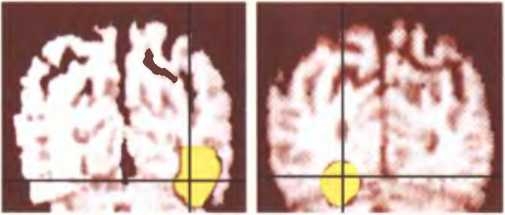

Новые действия, для которых требуется делать выбор, требуют большей мозговой активности, чем привычные действия. Здесь показан головной мозг человека, подбирающего слова, которые он собирается сказать. Активирующиеся при этом области мозга связаны с принятием решений и концентрацией внимания. На средних двух изображениях показан мозг после того, как человек практиковался до тех пор, пока произнесение подобранных слов не стало для него привычным, и соответствующие области мозга не перестали возбуждаться. Справа человек вновь подбирает новые слова, и данные области вновь активируются.